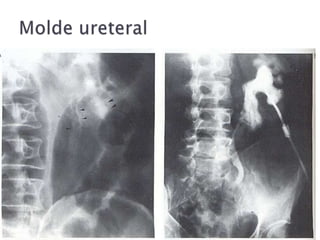

 Pielografía retrógrada

 Indicada en UIV muda

 Procedimiento previo a la derivación urinaria

por litiasis, fibrosis, atrapamiento ureteral

benigno o maligno

 Desv.: requiere soporte endoscópico o

fluoroscópico

 Pielografía retrógrada Indicada en UIV muda  Procedimiento previo a la derivación urinaria por litiasis, fibrosis, atrapamiento ureteral benigno o maligno  Desv.: requiere soporte endoscópico o fluoroscópico